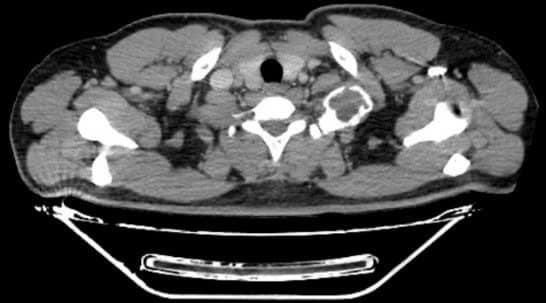

Bệnh nhân Hà Minh V. (nam, 33 tuổi, Cẩm Thủy, Thanh Hóa) đi khám vì đau tức nhẹ vùng vai trái khi vận động cánh tay kèm cảm giác tê bì nhẹ cánh tay trái, khám và chụp cắt lớp vi tính lồng ngực phát hiện u xương sườn kích thước lớn vị trí cung sau xương sườn số 1, u choán gần toàn bộ vùng hõm đỉnh.

Kết quả chụp cắt lớp vi tính ngực cho thấy hình ảnh khối u cung sau xương sườn số 1 kích thước 5x6cm, choán gần toàn bộ vùng hõm đỉnh bên trái, mặt trước của khối u dính sát phía sau động mạch, tĩnh mạch dưới đòn trái, bờ trên và sau của khối u nằm sát đám rối cánh tay, bờ dưới của khối u dính vào đỉnh phổi trái.

Nhận định về ca bệnh này, TS.BS Nguyễn Khắc Kiểm, Trưởng khoa Ngoại lồng ngực, Bệnh viện K chia sẻ: “Bệnh nhân có khối u xương kích thước lớn, tuy nhiên u nằm ở vị trí cung sau và chiếm toàn bộ xương sườn số 1, do vị trí giải phẫu xương sườn số 1 và cấu trúc liên quan (cơ, mạch máu, thần kinh) nên việc đưa ra phương án lựa chọn đường tiếp cận u, cắt u sao cho thuận lợi, triệt căn nhất và tránh được các tai biến như chảy máu, liệt cánh tay trái là vấn đề rất khó khăn.

Với tỷ lệ u xương tại xương sườn số 1 là rất hiếm gặp nên chưa có phương pháp phẫu thuật tiêu chuẩn nào được thiết lập. Với u xương lành tính nói chung, việc phẫu thuật là phương pháp điều trị triệt căn.

Đối với các u xương ở xương sườn số 1 là cực hiếm gặp, u to gây chèn ép vào bó mạch máu và đám rối thần kinh cánh tay sẽ gây ra các biến chứng nghiêm trọng như hội chứng lỗ thoát ngực. Chúng tôi đã hội chẩn, đưa ra nhiều phương án để cân nhắc kỹ càng sau đó tư vấn cho người bệnh”.